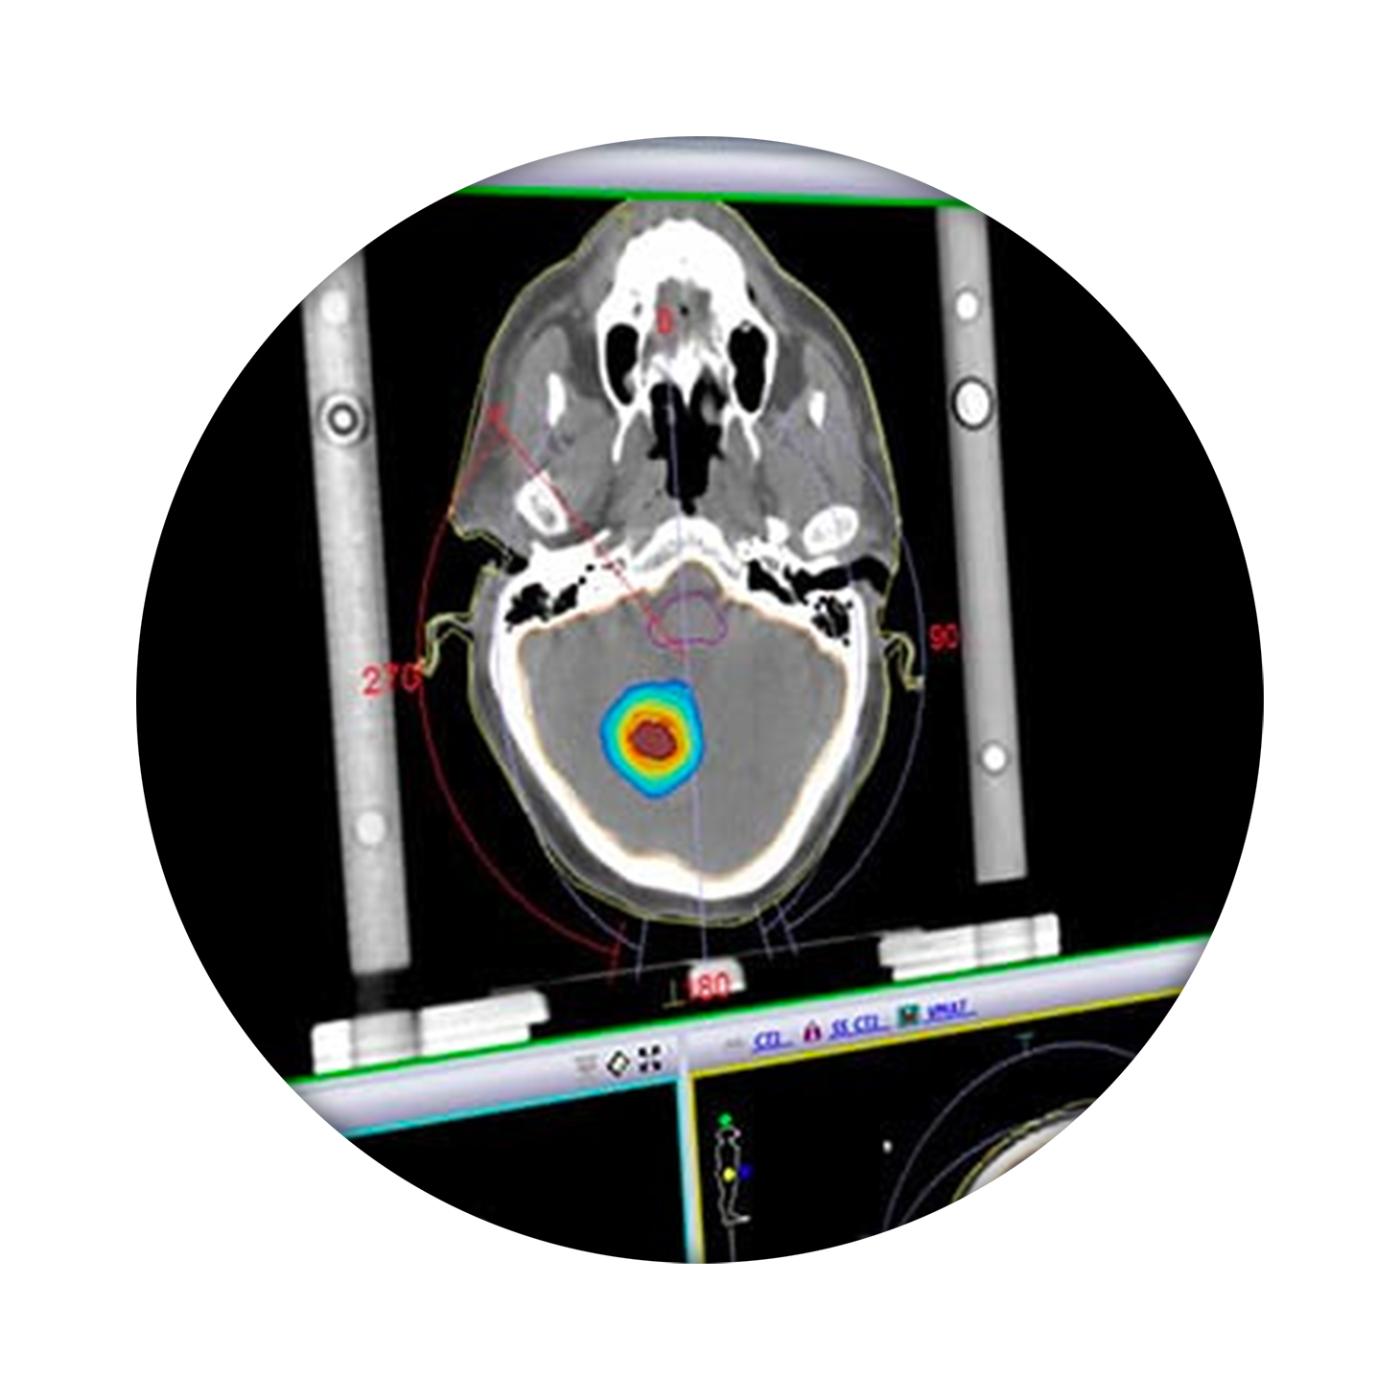

我科 Elekta Monaco 治疗计划系统 发布时间:2018/7/5 4:10:00       浏览次数:2756次

Monaco帮助临床医生提供最高标准的治疗。利用生物智能和标准化的计划解决方案,Monaco帮助临床医生了解患者生物学状态,同时提供快速有效的计划设计方案,将优化后的计划提交到治疗流程。